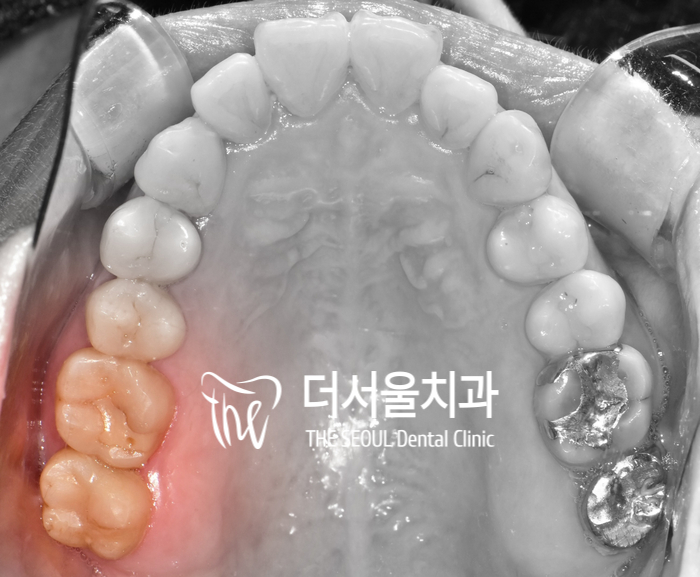

구내 사진으로 확인해봤을 땐

별다른 특이소견이 느껴지지 않았는데요.

이것이 인접면 우식의 문제라 할 수 있죠.

겉으로 보기에는 아무런 티도 나지 않기에

스스로 발견하는 것이 쉽지 않습니다.